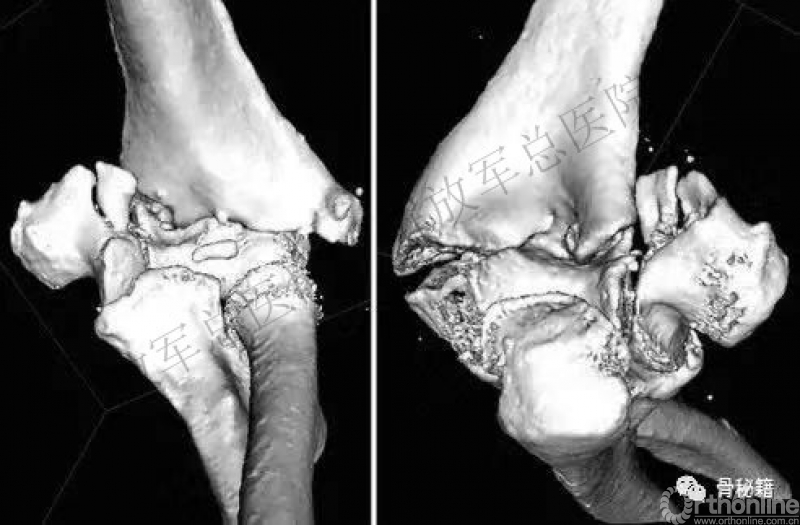

一、详细的术前评估

X线、CT、神经检查、等等。